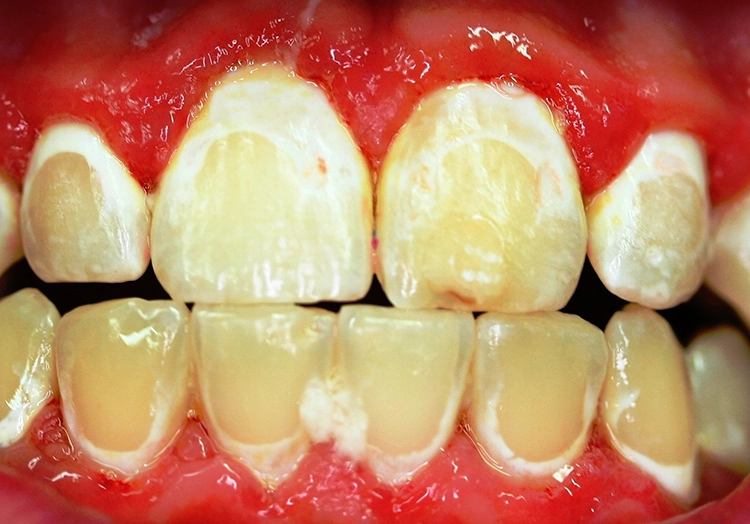

Dr. J. SchmoeckelAbb. 2: Die Frühkindliche Karies (früher „Nuckelflaschenkaries“ genannt) ist durch ein Auftreten flächiger kariöser Läsionen, die meist zunächst die Oberkieferschneidezähne betreffen, gekennzeichnet. Hauptursachen von ECC sind eine mangelhafte Zahnpflege beim Kleinkind in Kombination mit einem hochfrequenten Konsum zuckerhaltiger Getränke zwischendurch und/oder nachts.

Beim Kleinkind spielt primär die frühkindliche Karies eine Rolle, die initial meist durch kariöse Läsionen an den Oberkieferfrontzähnen gekennzeichnet ist (Abb. 2). Im permanenten Gebiss unterliegen die Kauflächen der durchbrechenden 1. und 2. Molaren insbesondere in der ca. 1,5 Jahre dauernden Durchbruchsphase einem erhöhten Kariesrisiko. Während kieferorthopädischer Maßnahmen mit festsitzenden Apparaturen bei Jugendlichen sollte besonderes Augenmerk auf die Beurteilung der Mundhygiene, wie dem Vorhandensein kariogener Plaque auf Kariesrisikoflächen (Abb. 3), und Kariesaktivität gelegt werden, um frühzeitig präventiv einzugreifen und klinische Bilder mit kariösen Läsionen an fast allen Zähnen möglichst zu vermeiden (Abb. 4).